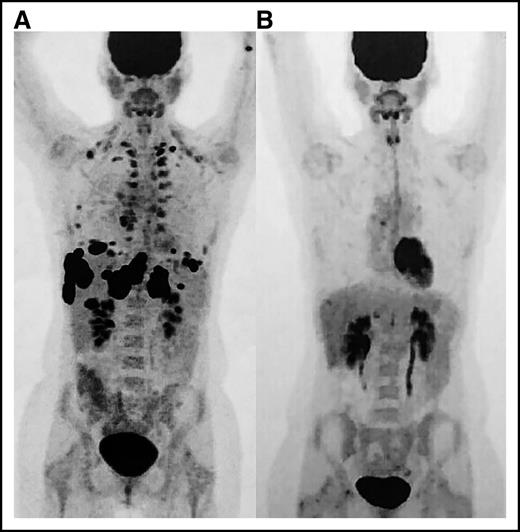

Positron emission tomography (PET) images. (A) Scan prior to initiation of nivolumab and (B) restaging PET after eighth cycle revealing complete remission.

The patient’s ANC markedly improved within 3 days, but recovery was transient and required another dose of IVIG 11 days after the first dose (Figure 1). Computed tomography showed a pronounced partial response where no therapy had successfully worked before. It was for this reason that nivolumab was restarted in addition to rituximab to preemptively treat autoimmune neutropenia. The patient never again experienced neutropenia and ultimately developed a complete remission within 4 months (Figure 2). Now 18 months from remission, she has remained relapse free with normal blood cell counts at the time of this article’s submission.